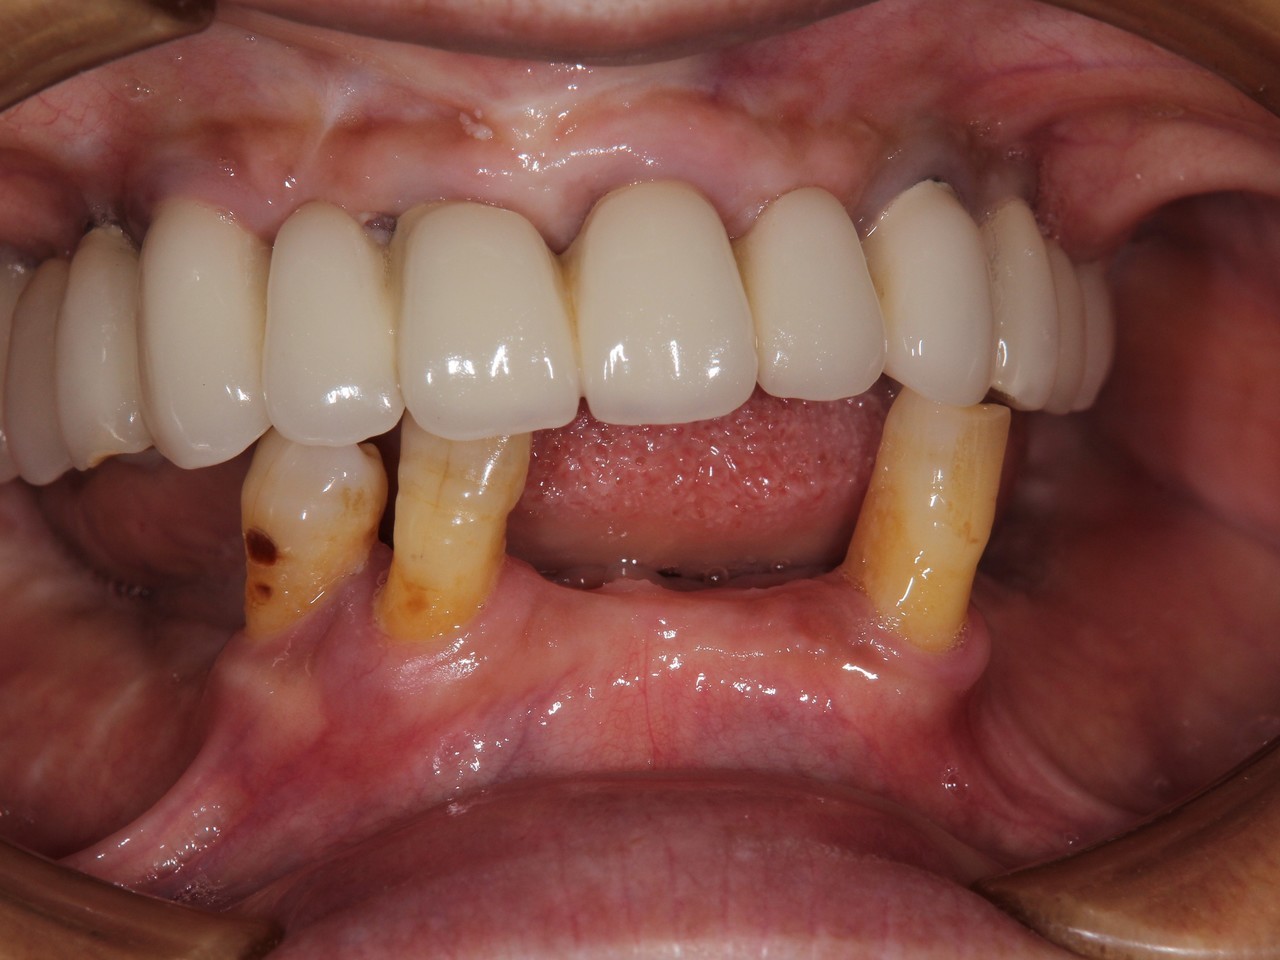

6本のインプラントで、12本の歯を並べる(下顎・仮歯代含む)

(裾野市在住 女性)

お口の中の状態

被せ物を外した状態

6本のインプラントを埋入し、12本の歯を並べています。第二大臼歯を作らない場合の理想的な治療法になります。

【下顎インプラント6本で12本の歯を回復するスクリュー固定タイプ】

インプラント手術:250,000円×6本=1,500,000円

静脈内鎮静法:0円

既製アバットメント:90,000円×6個=540,000円

メタルボンド:130,000円×12本=1,560,000円

マルチアバットメント:25,000円×6個=150,000円

連結料:10,000円×11カ所=110,000円

仮歯:50,000円×6本=300,000円

ポンティック:10,000円×6本=60,000円

ラジオグラフィックガイド(14本):23,000円

埋入ガイド(6本):73,000円

総額:4,316,000円+税